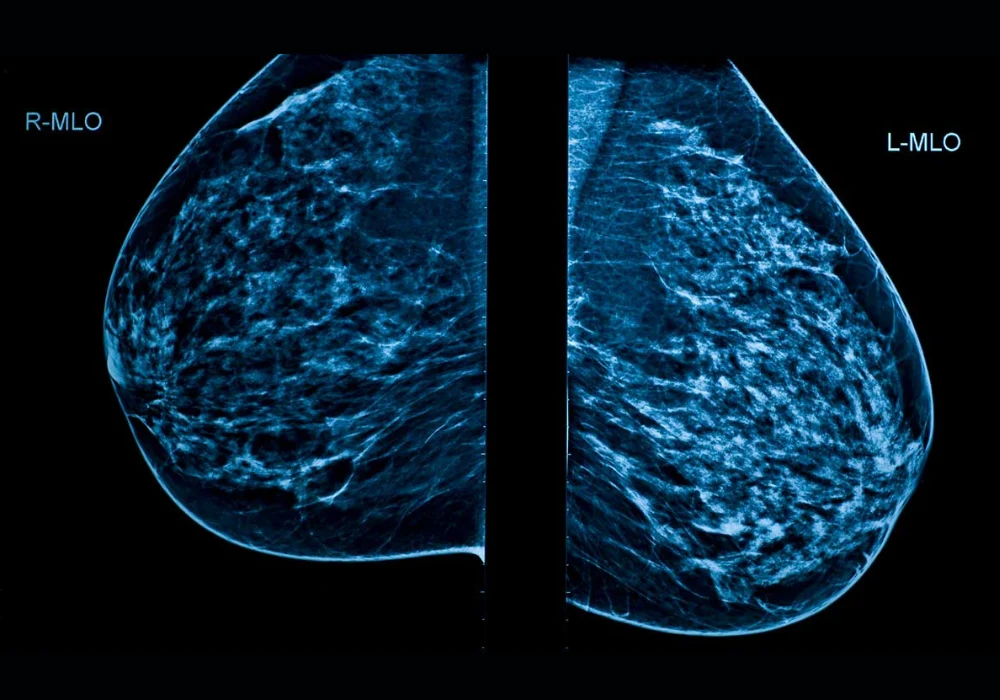

Breast cancer remains the most common cancer in women. While incidence has been rising, mortality has declined, supported by earlier diagnosis through mammography screening. Yet performance varies, with sensitivity reported at 80–98% and falling below 70% in women with dense breast tissue. Double reading can increase detection but is challenged by workforce constraints and concerns about higher recall. Artificial intelligence (AI) has emerged as an adjunct in breast imaging, with retrospective and screening-focused work suggesting potential benefits. Prospective evidence from diagnostic settings has been limited. A single-centre prospective evaluation conducted in a tertiary breast clinic assessed a commercially available AI system against radiologists with varying experience and explored how AI outputs might influence reassessment, while using histopathology and two-year follow-up as ground truth.

The evaluation included 1063 women aged over 40 who underwent two-view full-field digital mammography between April and July 2022. Mediolateral oblique and craniocaudal views were acquired on a single vendor platform. Five radiologists participated, including three with 5–10 years of experience, one resident and one with more than 20 years in breast radiology. Each breast was analysed independently, yielding 2126 examinations. Radiologists recorded Breast Imaging-Reporting and Data System (BI-RADS) assessments using the fifth edition lexicon, dichotomised as negative (BI-RADS 1–3) or positive (BI-RADS 0, 4–5). Decisions were made from the current mammograms alone without prior imaging, clinical data or adjunct modalities. Majority voting resolved discordant cases.

A standalone AI system (Lunit INSIGHT MMG version 1.1.7.1) analysed the same images, generated heatmaps and assigned lesion-level risk scores from 1 to 100. A threshold of 30.44 defined a positive AI result. The system also provided a quantitative breast density score, while radiologists classified density visually from A to D. Ground truth incorporated histopathology for cancers and a two-year negative follow-up for non-cancers. As a second step after a one-year washout, radiologists re-evaluated only AI-positive cases with AI markings available, enabling comparison of initial reads, AI performance and reassessment.

The cohort was enriched for dense breasts. Of 1063 women, 6.6% had type A density, 26.2% type B, 57.9% type C and 9.3% type D. Radiologist and AI density assessments showed moderate agreement with a kappa of 0.602. Across the study, 29 cancers were found in 28 women, and no interval cancers were observed during follow-up. The median tumour diameter was 21 mm.